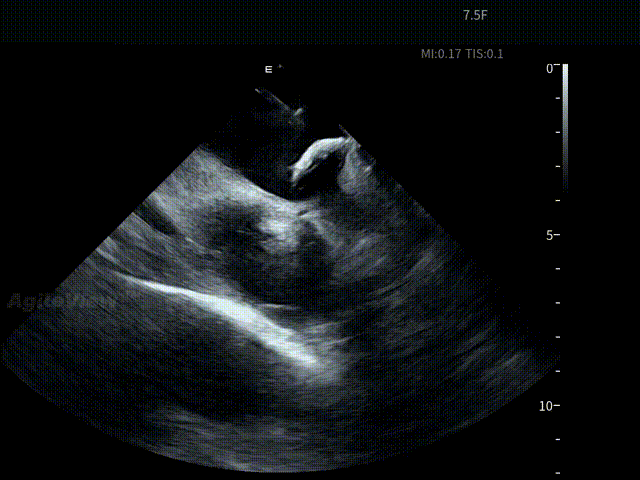

术中,基于AgileView™ 7.5Fr全球最细直径ICE导管的产品优势,周纬教授选择将ICE送入左房,以便更好地进行冷冻球囊的贴靠与位置的判断,在AgileView™ ICE实时影像的指导下, Arctic Front Advance Pro冷冻球囊导管消融导管安全进入左心房,先后完成双侧肺静脉隔离及顶部线隔离, ICE下可见导管贴靠良好,整个消融过程顺利,消融时间仅约25分钟,得益于超声设备清晰的成像质量,在顶部线隔离的时候可借助多普勒模式清晰的观察到球囊与组织的贴靠程度。 整个手术流程在ICE影像的指引下顺利完成,术中患者耐受良好,生命体征保持平稳。

顶部线第一次消融

第二次顶部线消融